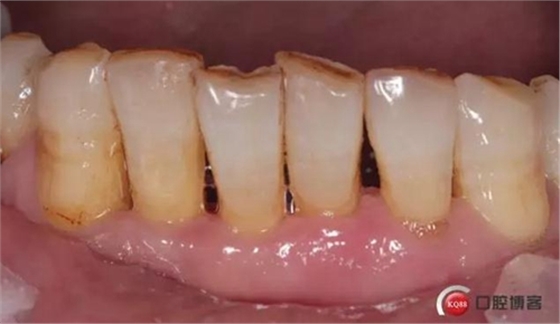

检查:口腔卫生状况欠佳,牙面可见大量色素附着,牙石II°,尤以下颌前牙舌侧及后牙颊侧为重。牙龈红肿,BI3-4°,PD下颌前牙区4-6mm。31松动III°,温度测试无反应,叩不适。32、41、42松II°+,32温度测试迟钝,叩(-)。

口腔宣教,全口龈上洁治,龈下超声刮治,手工根面平整。双氧水冲洗止血。指导刷牙方式。嘱卫生维护,一周复诊。

检查:口腔卫生状况尚可,下颌前牙区牙齿邻接可见食物残渣附着。牙龈色泽转淡。

检查:口腔卫生状况一般,下颌前牙区牙龈色泽尚可,牙龈位置退缩,松动度减轻。

检查:下颌前牙区PD1-3mm,牙龈色泽尚可,舌侧龈缘可见少量软垢附着。31松II°,32、41、42松I°+。